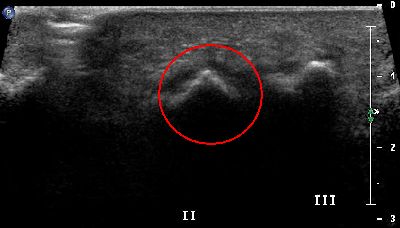

Sesamoide accessorio quinto dito (img. 01) Sesamoide accessorio quinto dito (img. 01)

Sesamoide accessorio quinto dito (img. 02) Sesamoide accessorio quinto dito (img. 02)

Sesamoide accessorio quinto dito (img. 03) Sesamoide accessorio quinto dito (img. 03)